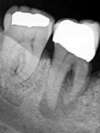

Le kyste (appelé granulome quand il fait moins de 5 mm) débute par une infection diffuse (présence de bactéries toxiques dans les racines de la dent) qui évolue en formant une poche de tissus infectés. Le kyste peut grossir sans douleur et sans signes extérieurs durant plusieurs années.

Le granulome ou le kyste peuvent avoir comme origine un choc ayant nécrosé la dent, une carie non soignée, ou encore un traitement des racines insuffisant ou contaminé par une réparation ou une couronne non étanche.

Leur découverte est le plus souvent fortuite, au cours d’une radiographie faite pour une autre pathologie par exemple.

Il est indispensable de faire un contrôle dentaire annuel, avec bilan radiographique, afin de ne pas passer à côté d’un kyste.